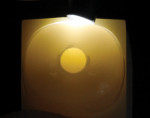

A recent ongoing study by Lucas et al compared a ceramic removal diamond bur (150 µm to 200 um) to a fine diamond bur for endodontic access.10 In the study, a 2.5 mm access hole was placed in the center of 1 mm thick bonded lithium disilicate and 0.8 mm cemented zirconia crowns (Figure 1). The access holes were examined with transillumination and no radial cracks were noted (Figure 2). Surprisingly, the fine diamond bur caused more edge chipping around the endodontic access hole (Figure 3 and Figure 4). After testing in compression (Figure 5), it was determined that accessing the crowns with a fine diamond led to a lower crown fracture strength in lithium-disilicate crowns and similar fracture strength with zirconia crowns. Additionally, the ceramic removal diamond bur was more efficient in cutting through both zirconia and lithium disilicate.